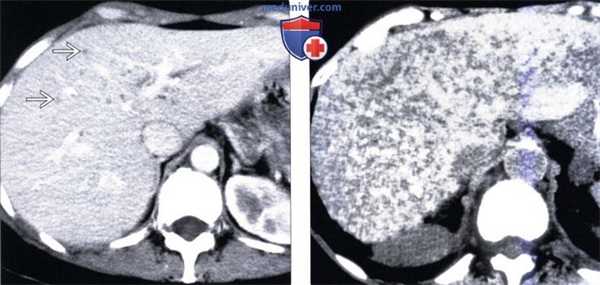

(Слева) На КТ срезе у этой же пациентки определяется, что очаги имеют приблизительно одинаковые небольшие размеры. Если как следует присмотреться, можно заметить узловое утолщение стенки наибольших из них.

(Справа) На поперечной сонограмме у этой же пациентки, выполненной в этот же день после КТ, определяется только небольшое количество «кистозных» очагов, видны также многочисленные мелкие эхогенные узлы, диффузно «разбросанные» по всей паренхиме печени, представляющие собой билиарные гематомы меньшего размера, содержащие, предположительно, больше фиброзной ткани, и меньше — жидкости. (Слева) На КТ у пациента с хроническим вирусным гепатитом визуализируются множественные мелкие кистозные образования; стенка некоторых из них деформирована и содержит узлы. Эти изменения типичны для билиарных гамартом, однако крайне редко могут являться признаком гепатоцеллюлярного рака (ГЦР).

(Справа) На поперечной сонограмме у этого же пациента визуализируется один из нескольких эхогенных очагов, а также большее количество кистозных образовании. Отсутствие изменений со стороны очагов при последующих лучевых исследованиях в течение нескольких лет позволяет подтвердить, что они, скорее всего, представляют собой билиарные гамартомы.